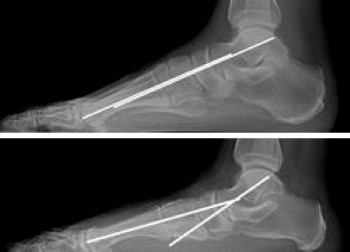

X-ray of flatfoot

(Top)  An X-ray of a normal foot. Note that a line through the center of the ankle bone (talus) and a line through the rest of the foot are parallel, indicating a normal arch. (Bottom)  In this X-ray the lines diverge, which is consistent with flatfoot deformity.